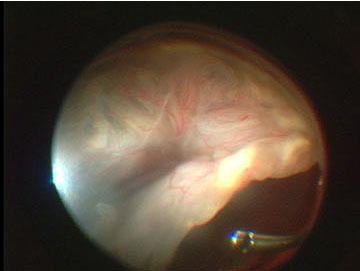

Images featured on this website were captured with A.V.I. Video Adapter and are the sole property of Advanced Visual Instruments, Inc. All retinal images were captured through A.V.I. Stereo Inverter and A.V.I. Panoramic Lenses. All images owe their superb quality of anatomical detail to the unique design and fine optics of A.V.I. products. To facilitate web viewing the images had been reduced in size.